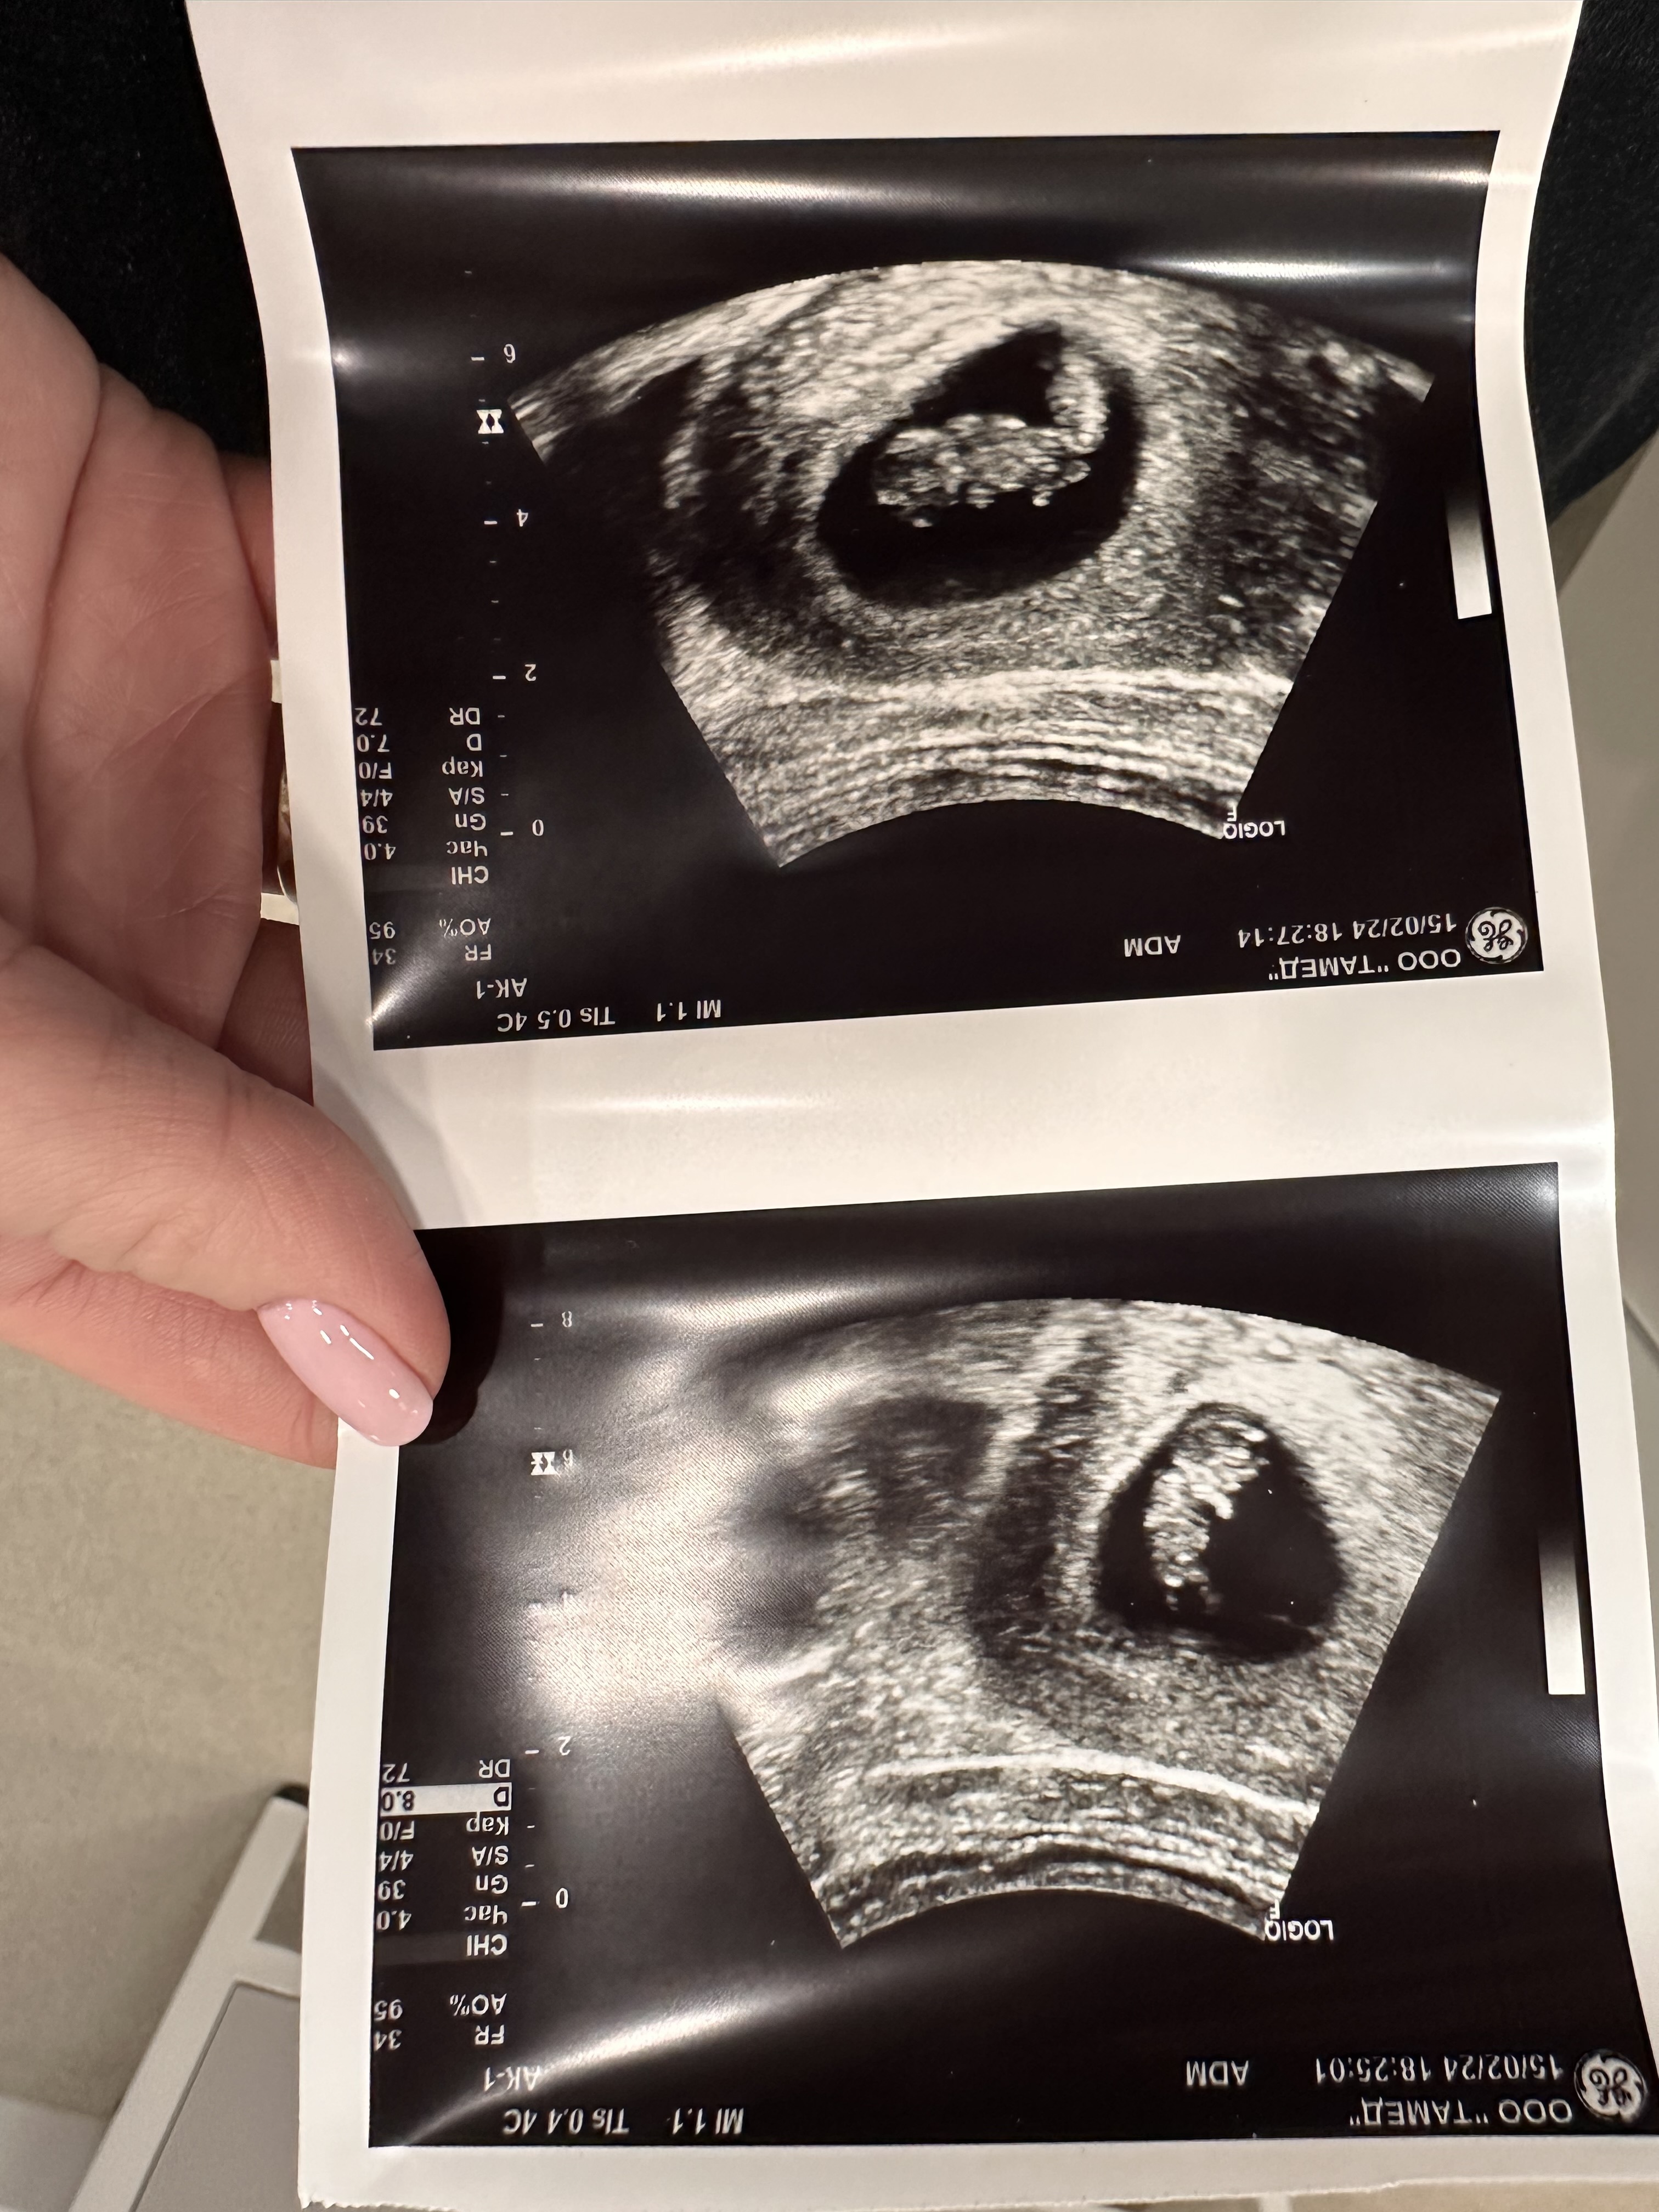

Изображение Вот моя однояйцевая двойня. Это значит, что оплодотворенная яйцеклетка поделилась. Не важно были в роду двойняшки или нет) у меня и у супруга никого нет ни близнецов ни двойняшек

Анаставитушка, на первой фотке один малыш, на второй фотке второй малыш Сфоткать их вместе сложно До 7-8 недели не видели второго малыша На 8.5 увидели двоих

An, у меня в 6 недель вообще никого не было, только пустое плодное яйцо и желточный мешок, а вот уже к 8 неделе двоих она нашла. Поэтому я в ступоре сидела, не сразу осознала. Спасибо за отзыв 🙏

А в чем сомнения? В компетенции специалиста? Она же сказала два сердцебиения. На одном фото УЗИ никогда не будет 2 эмбриона как на картинке. ТК они все время перемещаются. Потому сначала один будет хорошо виден, потом второй если поднадавить и под другим углом датчик поставить. Тут важнее в заклчении моноамниотическая или диамниотическая двойня.

Ну и размеры важны , конечно. Важно чтобы не сильная разница в размерах была. (На фото УЗИ, повторюсь не смотрите, там ракурсы разные)

Пойдете в марте, там и спросите какая двойня, точно монохориальная(одна плацента), а вот Момо моно или моно ди (одна или две амниотические оболочки) - вопросы . У меня тоже разные эмбрионы были, пугали что один может замереть до 10 недель. Но все норм. Они и сейчас разные, но в пределах нормы. (Тьфу тьфу тьфу)

Анаставитушка, а чего тогда сомневаться и удивляться? Или сомневаетесь в компетенции врача? На фото две горошины)

А что вас смущает? 2 бусики же на фото))) мои поздравления.

Анаставитушка, ракурс такой. Что она вам написала моно моно или моно ди? У моих просто была перегородка видна и вопросов не было.